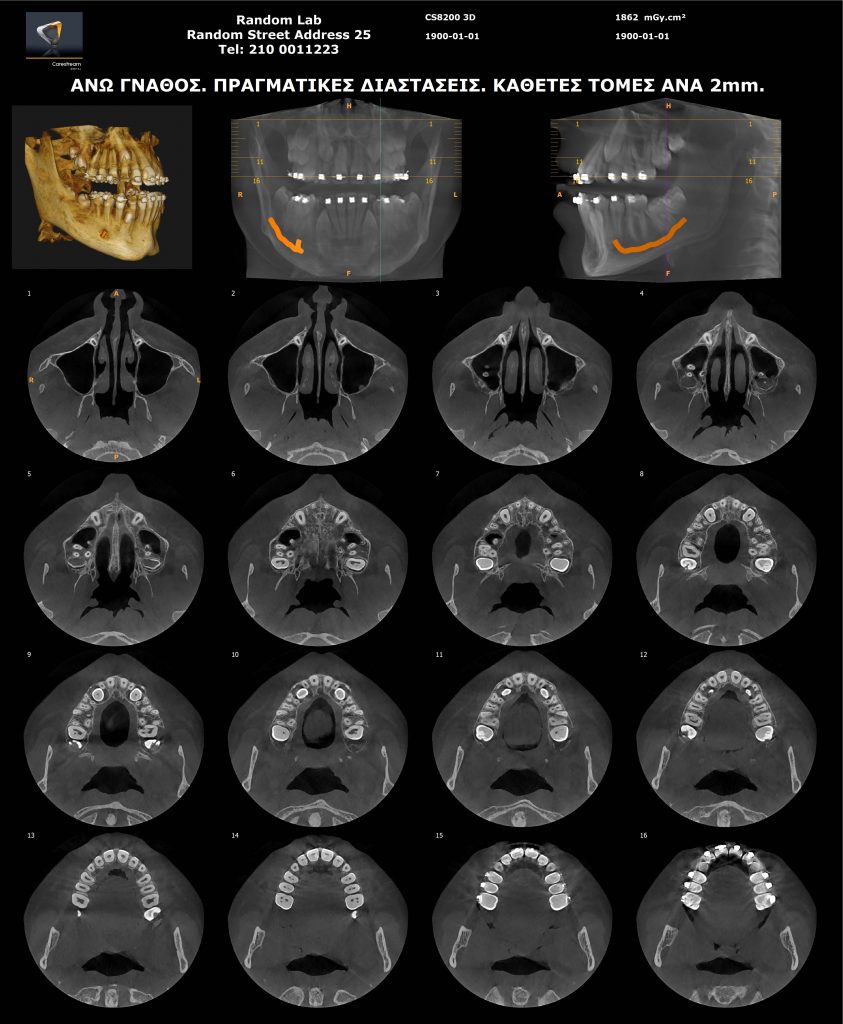

Ογκομετρικός Τομογράφος

- Oγκομετρικό τομογράφο – CBCT (3D) πολλαπλών οπτικών πεδίων, αξεπέραστης ποιότητας εικόνας.